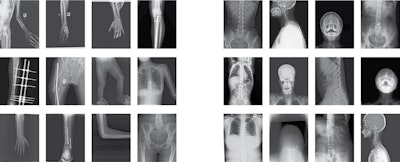

The dataset includes 4,083 images that two expert radiologists and an orthopedist have manually annotated for bone fracture classification, localization, and segmentation, lead co-authors Iftekharul Abedeen and Md. Ashiqur Rahman of the Islamic University of Technology in Gazipur, Bangladesh, explained.

To address the knowledge gap, the group first collected 14,068 x-ray scans from three hospitals and diagnostic centers in Bangladesh taken between 2021 and 2022. They culled 4,083 normal and abnormal images of the hand, leg, hip, and shoulder regions, then identified the presence and number of fractures on each image.

In total, out of 4,083 images, the dataset contained 717 images that had 922 instances of fractures. The age of subjects in the dataset ranged from eight months to 78 years old.